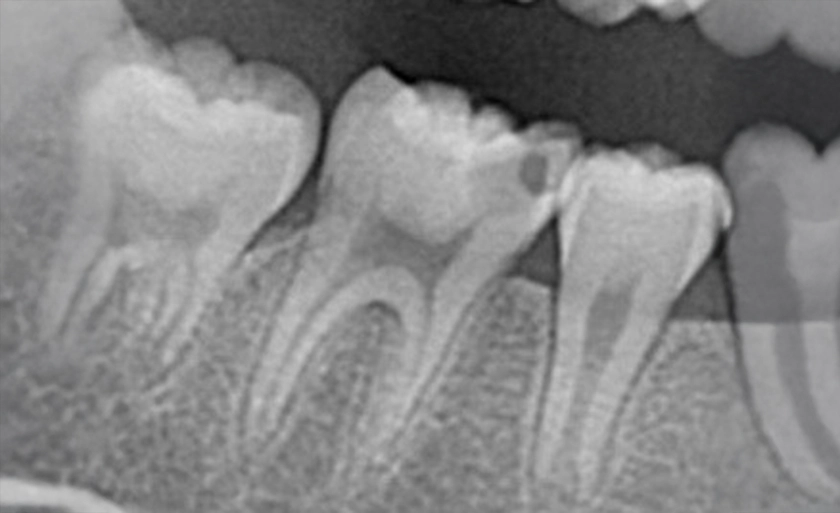

実際のレントゲン写真

②虫歯を除去していくと、感染して柔らかくなっている部分が出てきます。最初の穴より大きい範囲で、虫歯があるのがわかります。